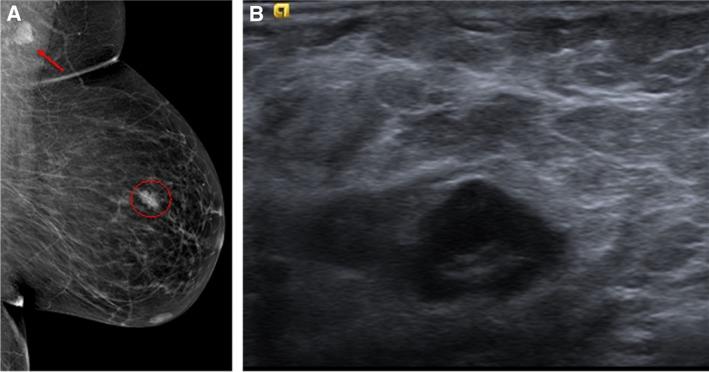

The detection of lymph node metastasis affects the management of patients with primary breast cancer significantly in terms of staging, treatment, and prognosis. The main goal for the radiologist is to determine and detect the presence of metastatic disease in nonpalpable axillary lymph nodes with a positive predictive value that is high enough to initially select patients for upfront axillary lymph node dissection. Features that are suggestive of axillary adenopathy may be seen with different imaging modalities, but ultrasound is the method of choice for evaluating axillary lymph nodes and for performing image-guided lymph node interventions. This review aims to provide a comprehensive overview of the available imaging modalities for lymph node assessment in patients diagnosed with primary breast cancer. IMPLICATIONS FOR PRACTICE: The detection of lymph node metastasis affects the management of patients with primary breast cancer. The main goal for the radiologist is to detect lymph node metastasis in patients to allow for the selection of patients who should undergo upfront axillary lymph node dissection. Features that are suggestive of axillary adenopathy may be seen with mammography, computed tomography, and magnetic resonance imaging, but ultrasonography is the imaging modality of choice for evaluating axillary lymph nodes. A normal axillary lymph node is characterized by a reniform shape, a maximal cortical thickness of 3 mm without focal bulging, smooth margins, and, depending on size, a discernable central fatty hilum.

临床意义